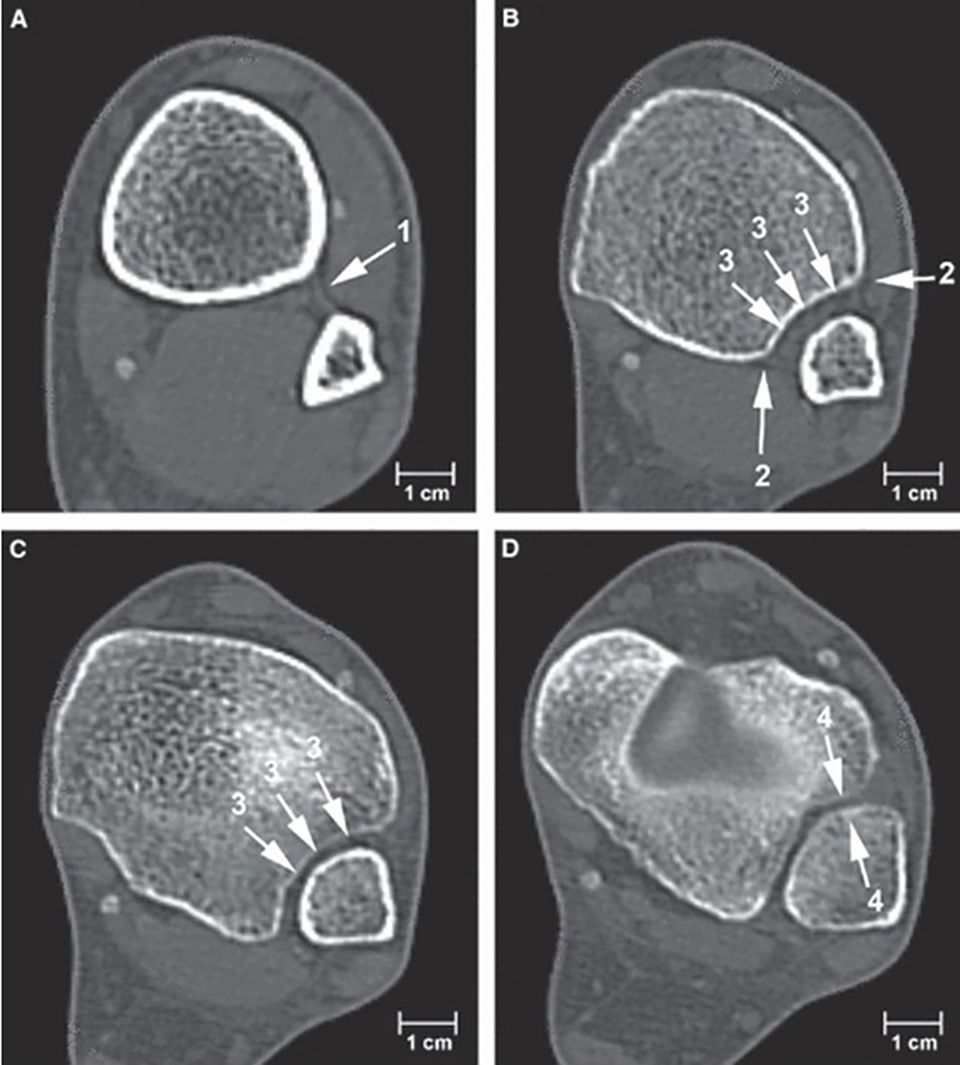

Computertomography (Figure 10)

CT scanning is an accurate method of detecting syndesmotic injuries. CT scanning of both ankles allows determination of fibular shift, rotation, shortening and the exact location of bony avulsions. Care is taken to evaluate the fibular rotation and tibiofibular distance in the horizontal plane at exactly the same level as on the uninjured side. Coronal reconstruction allows exact determination of a lateral shift of the talus and measuring of the fibular length. Generally, side-to-side differences of more than 2 mm are considered pathologic. In a recent study the three most responsive CT measurements for detecting isolated syndesmotic malreduction were described. [28] The clear space for lateral translation (Leporjärvi), the anterior tibiofibular distance for posterior translation as well as the talar dome angle for external rotation of the fibula (Nault). In diagnostic meta-analysis, the pooled sensitivity and specificity were 0.67 and 0.87 for CT respectively.[27]